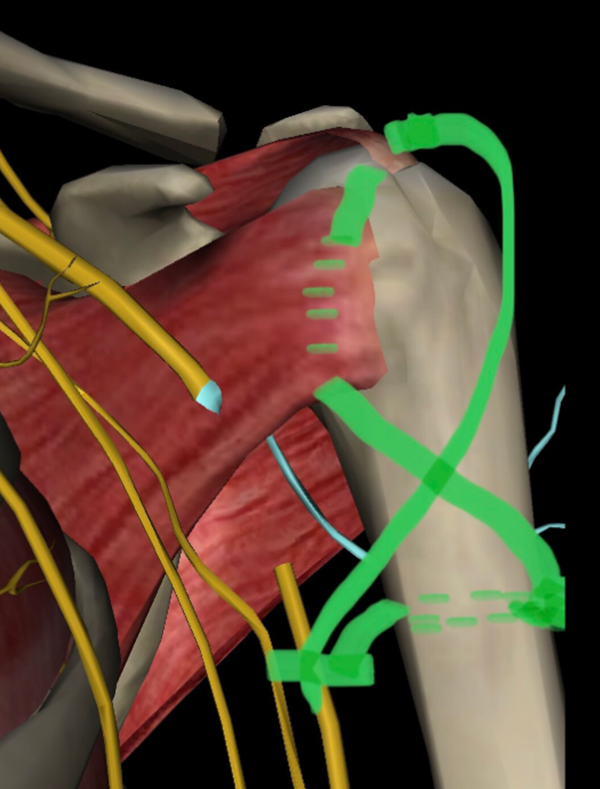

3、双套固定技术(团队推荐技术)

(1)一旦肱骨头与肱骨干相互之间达到满意的位置,打入两枚2mm克氏针,针尖到达肱骨头软骨下骨,复位质量也可通过在上肢外展80°时透视轴位片来检查,达到初始稳定。

(2)骨折部位下方3~4cm,在肱二头肌腱沟两侧钻孔穿钢丝,3.2cm钻头横形钻孔,穿过2条钢丝,分别经冈上肌腱下方及大小结节,以2个“8”字形固定(或胸骨钢丝固定)。

图12 带针芯针穿过肩胛下肌腱、小结节、肱骨头,由复位的大结节和附着的肩袖处穿出,穿过钢丝,再经肱骨干近端横形孔穿过,8字拧紧固定

第一个“8”穿冈上肌腱下,固定大结节;

第二个“8”穿肩胛下肌腱下,固定小结节,再经肱骨头,再穿冈上肌腱下,固定大结节;分别经肱骨干近端横行孔穿过,“8”字打结固定。

(3)修复肩袖

分别在冈上肌腱、冈下肌腱、和肩胛下肌止点处置入0号微乔线,同时把这些缝线都穿过钢板的缝线孔备用。好处是这些缝线既是复位骨折的把手,也是术闭缝合肩袖,加强骨折稳定的重要保障。

注意间断缝合冈上肌前缘和肩胛下肌上缘之间的旋转间隙,缝合闭合肩袖。